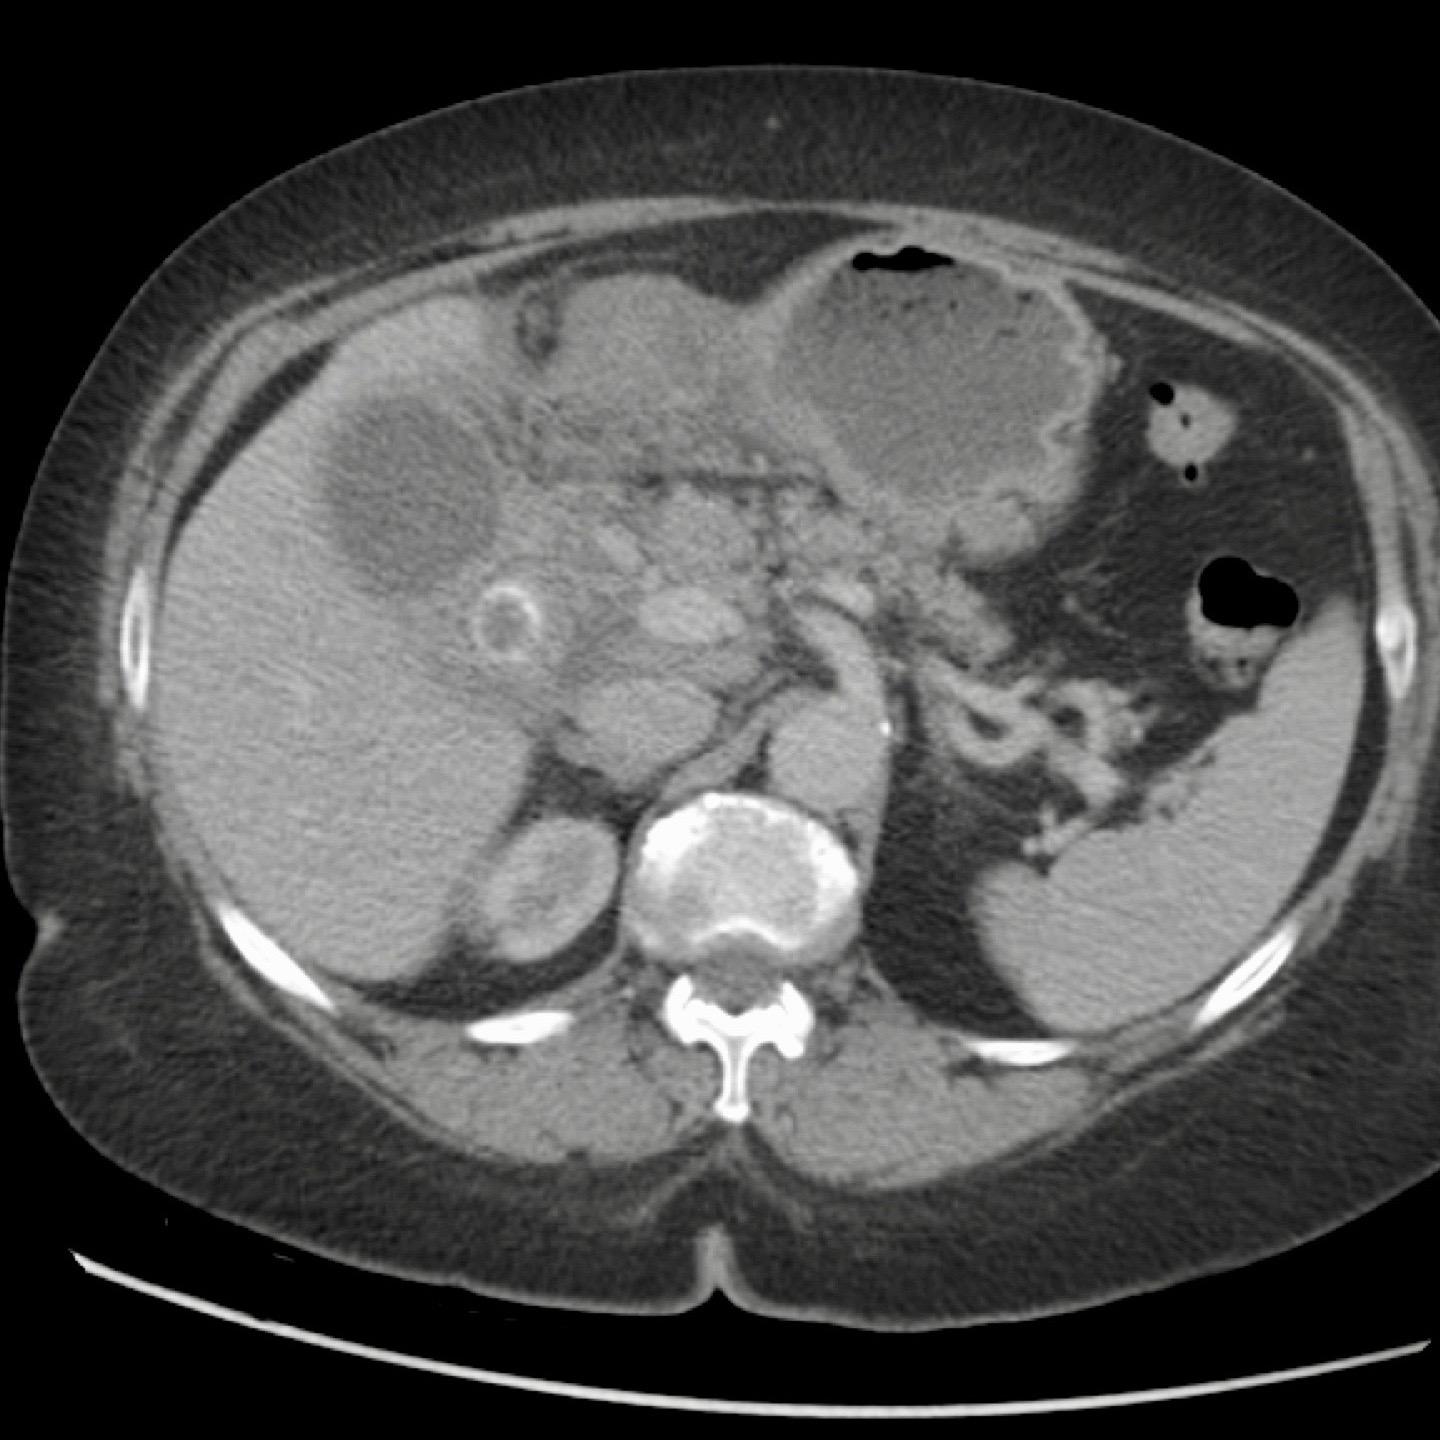

Hình ảnh của một bệnh nhân được nghi ngờ lâm sàng là thủng dạ dày.

CT cho thấy một số sỏi trong túi mật có hình dạng tròn.

Siêu âm bổ sung xác nhận rõ ràng tình trạng phình to túi mật (đầu mũi tên).